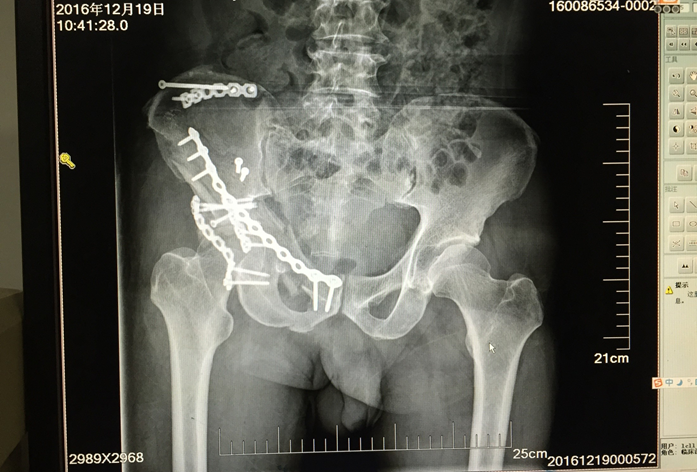

中西医结合治疗骨折是本科的特色;除了运用最先进的手术技术,科室还开展最传统的手法复位小夹板外固定技术,配合自行研发的中药外敷,给患者更好、更多的选择。小夹板固定和骨折微创技术治疗四肢骨折,疗效好,恢复快,效果达到国内先进水平。